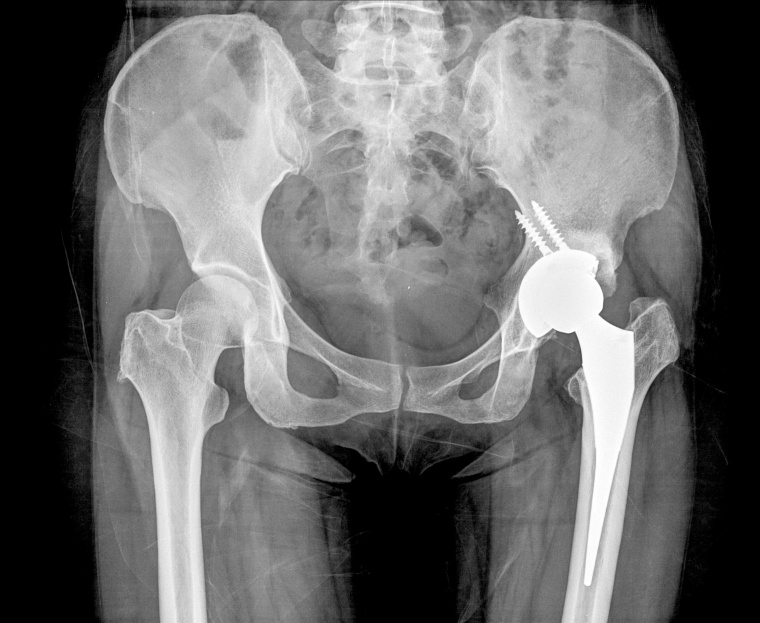

Künstliche Hüftgelenke wiederum werden überwiegend – in 77 % der Fälle – direkt in den Knochen hineingepresst. Die Vor- und Nachteile des jeweiligen Verfahrens und aktuelle Erkenntnisse, welche Art der Verankerung wem heute zu empfehlen ist, waren Themen der Online-Pressekonferenz der AE – Deutsche Gesellschaft für Endoprothetik.

Bei der „Press-Fit“-Verankerung verklemmen die Ärzte das Implantat quasi im Knochen. „Das Knochenlager wird dazu vorher passend zu den Abmessungen der Prothese in etwas kleinerer Größe vorbereitet“, erläutert die Orthopädin und Unfallchirurgin. Dies erzeugt einen sofortigen Halt. „Durch das darauffolgende Anwachsen des Knochens an die Implantatoberfläche wird die Prothese dann dauerhaft verankert.“